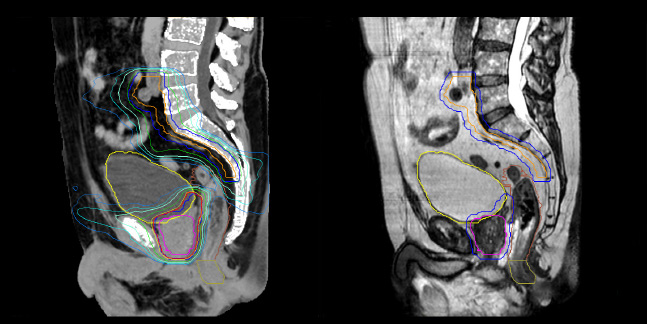

Dr. Champion appreciates that MRCAT Pelvis also enables rectal cancer simulation in the prone position, allowing the digestive anatomy to be moved away from the treatment volume by projecting them forward.

“The irradiation volumes for a rectal cancer are essentially posterior and lateral, so good sparing of the digestive structures improves tolerance of the treatment,” he says. “Prone positioning can also be applied to anal cancer simulation. This position enables the gluteal muscles to be moved apart, which significantly reduces the toxicity associated with radiation concentrating in the folds.”

MRCAT Pelvis also allows an up to 36-centimeter FOV in the feet-head direction, permitting creation of treatment plans covering extended pelvic targets.

“The large field-of-view is definitely useful and a must-have functionality,” Dr. Champion observes. “For several patients, we have treated the lymph nodes where the radiation fields are longer than 30 centimeters. In our practice, contouring of the pelvic lymph node areas is indicated in prostate cancers of intermediate or high risk. Rectal and anal canal cancer are also irradiated in the lymph node drainage areas. The cranial limit of this elective lymph node irradiation extends up to the aortic bifurcation, which often corresponds to the L4-L5 vertebral disc.”

Philips MRCAT (MR for Calculating ATtenuation) provides exceptional soft tissue contrast for target and OAR delineation, in addition to the Hounsfield units needed for dose calculations. This permits an MR-only radiotherapy planning workflow. Philips pioneered MR-only radiotherapy with the introduction of MRCAT Prostate, followed by the expansion to the whole pelvis with MRCAT Pelvis. This application can be used for a broad range of pelvic indications, including cancers in the prostate, rectum, bladder, anal canal and cervix. Next to MRCAT Pelvis, MRCAT Brain is available for radiotherapy planning of primary and metastatic soft-tissue tumors in the brain.